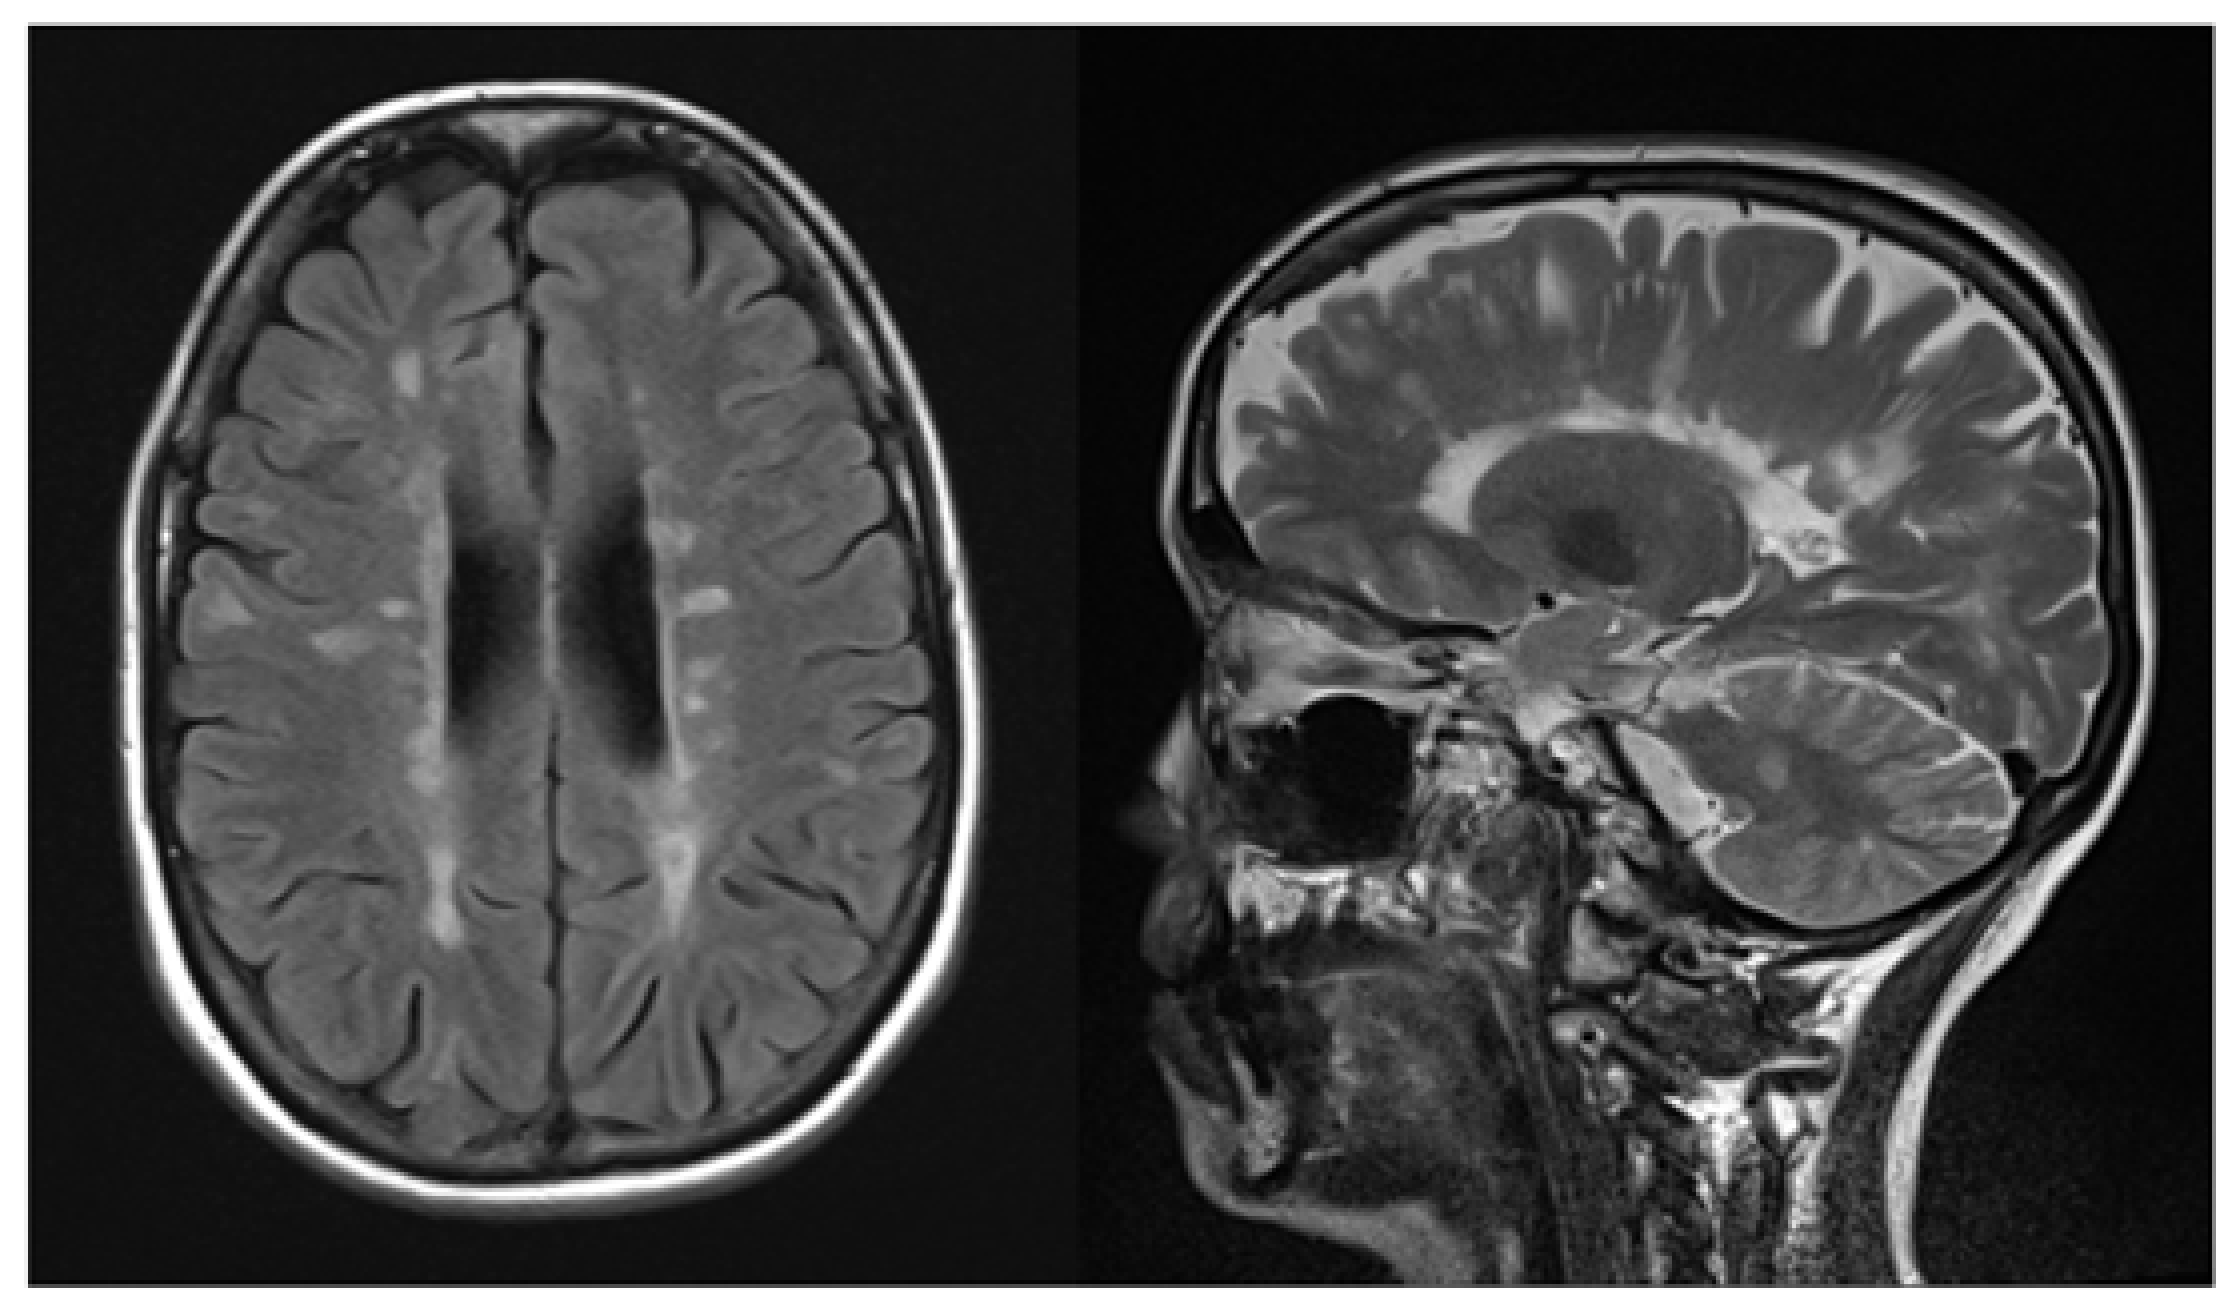

2. Case Report